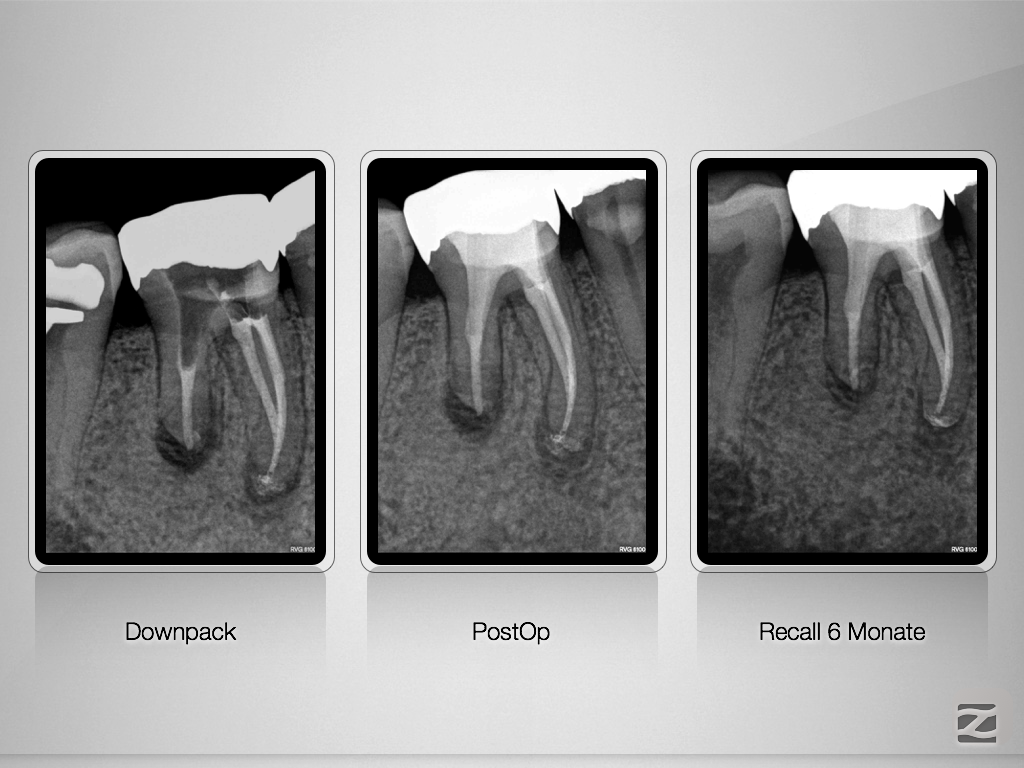

Externe Resorption